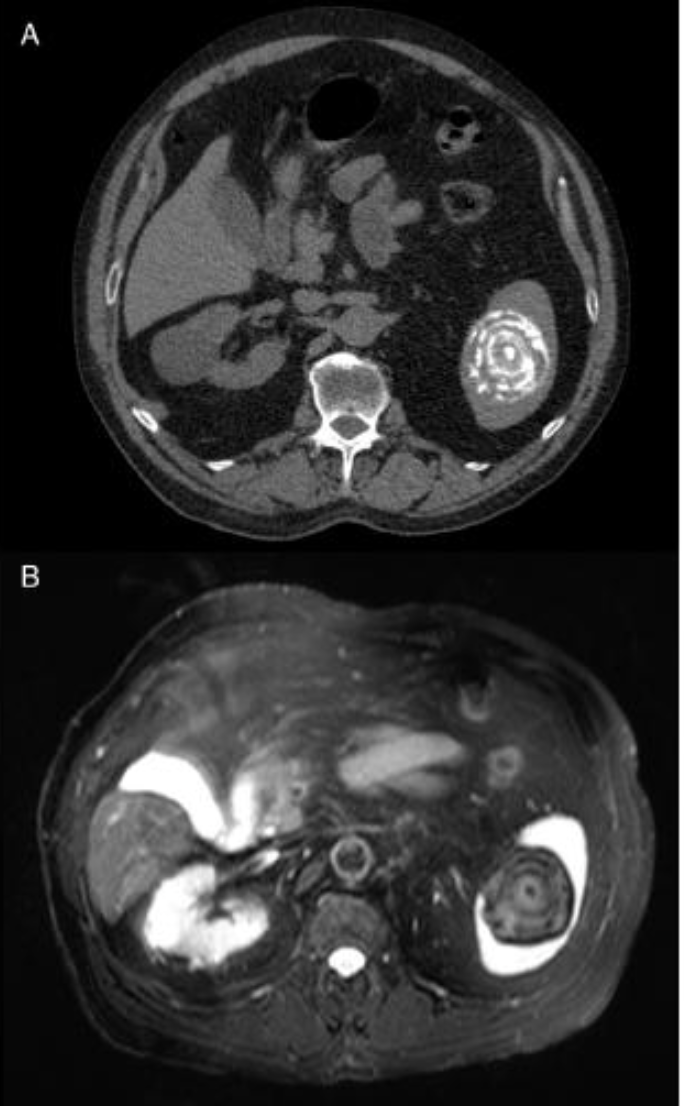

Dx?

Brucellosis: solitary, large (>2cm) targetoid calcified, splenic lesion.